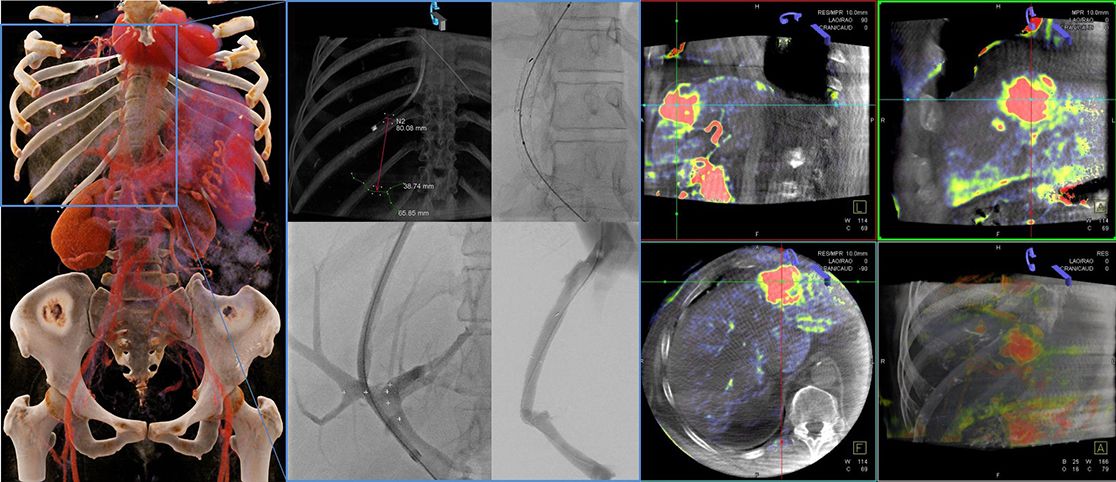

- Evaluation des Cone-Beam CT bei TACE, SIRT, Bronchialarterienembolisation, Blutungen, TIPSS etc.)

Parenchymal Blood Volume Assessed by C-Arm-Based Computed Tomography in Immediate Posttreatment Evaluation of Drug-Eluting Bead Transarterial Chemoembolization in Hepatocellular Carcinoma.

Syha R, Grözinger G, Grosse U, Maurer M, Zender L, Horger M, Nikolaou K, Ketelsen D. Invest Radiol. 2016 Feb;51(2):121-6.

Assessment of the parenchymal blood volume by C-arm computed tomography for radioembolization dosimetry.

Grözinger G, Kupferschläger J, Dittmann H, Maurer M, Grosse U, la Fougère C, Nikolaou K, Syha R, Ketelsen D. Eur J Radiol. 2016 Sep;85(9):1525-31.